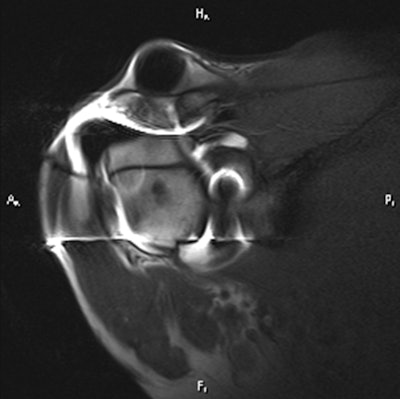

The study included 100 consecutive patients with a variety of injuries and abnormalities who were scanned using MRI, MR arthrography, and CT arthrography. Patients received a combination of gadolinium and CT contrast agent at the time of the arthrogram so CT could be performed after the procedure if a metallic artifact interfered with the MRI scan.

The results were reviewed retrospectively by two musculoskeletal radiologists. MRI uncovered 42 full-thickness supraspinatus tendon tears, 32 superior labral anterior to posterior (SLAP) tears, 19 anterior labral tears, and 16 posterior labral tears.

Meanwhile, MR arthrography showed 51 full-thickness supraspinatus tendon tears, 46 SLAP tears, 22 posterior labral tears, and 24 anterior labral tears. Of these, 14 SLAP tears, nine supraspinatus tendon tears, six posterior labral tears, and five anterior labral tears were not detected on conventional MRI.